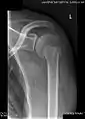

X-ray at left shows anterior dislocation in a young man after trying to get up from his bed. X-ray at right shows same shoulder after reduction and internal rotation, revealing both a bony Bankart lesion and a Hill-Sachs lesion. X-ray at left shows anterior dislocation in a young man after trying to get up from his bed. X-ray at right shows same shoulder after reduction and internal rotation, revealing both a bony Bankart lesion and a Hill-Sachs lesion.